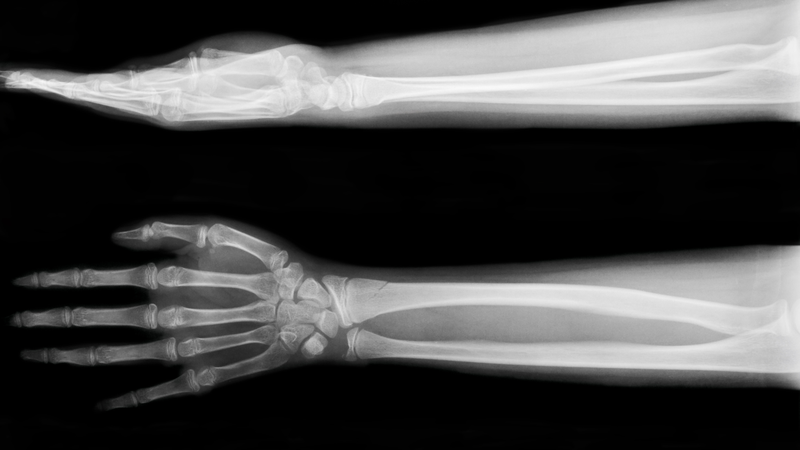

Cẳng tay, bộ phận nối liền giữa khớp cổ tay và khớp khuỷu tay, đóng vai trò quan trọng trong cử động linh hoạt của bàn tay. Tuy nhiên, cấu trúc phức tạp bên trong cẳng tay tiềm ẩn nhiều nguy cơ tổn thương mà mắt thường khó có thể quan sát. Do đó, chụp X-quang xương cẳng tay trở thành "cánh tay đắc lực" cho y khoa trong việc chẩn đoán và điều trị hiệu quả các bệnh lý liên quan. Bài viết dưới đây sẽ giúp bạn hiểu rõ hơn về kỹ thuật chụp X-quang xương cẳng tay thẳng nghiêng.

Chụp X-quang xương cẳng tay ở các tư thế thẳng và nghiêng là một kỹ thuật hình ảnh phổ biến được sử dụng để đánh giá chính xác các tổn thương ở vùng cẳng tay. Kỹ thuật này cho phép chụp toàn bộ cẳng tay ở tư thế ngửa, bao gồm cả khớp khuỷu tay và khớp cổ tay. Hình ảnh được chụp từ hai góc nhìn khác nhau là thẳng và nghiêng.

Các chấn thương thường cần chụp X-quang xương cẳng tay bao gồm: Gãy xương cẳng tay, trật khớp cẳng tay, viêm xương, viêm khớp, loãng xương, nhiễm trùng và các khối u xương lành tính hoặc ác tính. Đặc biệt, gãy hai xương cẳng tay là loại tổn thương cần thiết phải chụp X-quang xương cẳng tay ở tư thế thẳng và nghiêng.